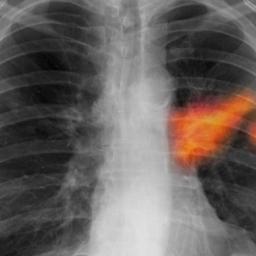

Exposure to mixture of common chemicals may trigger cancer, scientists find

One in five cancers may be caused when common chemicals – deemed safe on their own – blend lethally inside the human body, study revealsChemicals deemed safe to humans may blend lethally together inside the human body to cause cancer, a report says.Researchers, including New Zealand scientist Dr Linda Gulliver, have released findings into possible links between common chemicals and the development of cancer. Continue reading...

NHS cancer guide for GPs and patients could save 5,000 lives a year, says Nice

Guidance on symptoms and tests drawn up by the National Institute for Health and Care Excellence for doctors and patients could transform cancer care in UKDoctors are being advised to extend cancer tests to half a million more people a year under new guidelines which could eventually prevent 5,000 deaths a year.Thousand of lives will be saved every year if GPs and patients act on new NHS guidance, which details for the first time the symptoms that could indicate cancer. Continue reading...